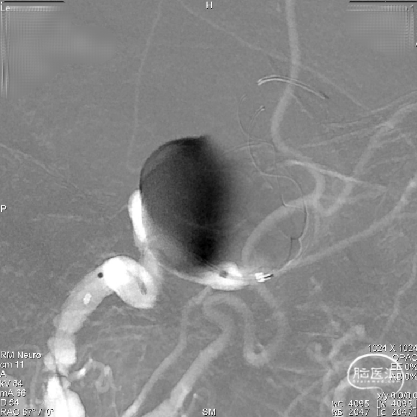

导丝按摩:

为防止支架未完全贴壁,即刻采用“massage技术”从远至近对Tubridge血流导向密网支架每个节段进行充分按摩。

术后即刻造影显示,支架打开良好、贴壁充分,囊内有明显的滞留。

血流导向密网支架作为治疗大/巨大型颅内动脉瘤各文献中明确确定了它的疗效价值,本病例我们首选采用血流导向密网支架为患者进行治疗。在本次使用Tubridge血流导向密网支架(改进版)治疗颈内动脉巨大动脉瘤过程中,支架头端锚定精准、打开顺利,Tubridge(改进版)良好的通过性和支架的充分贴壁确保了手术治疗的安全性。